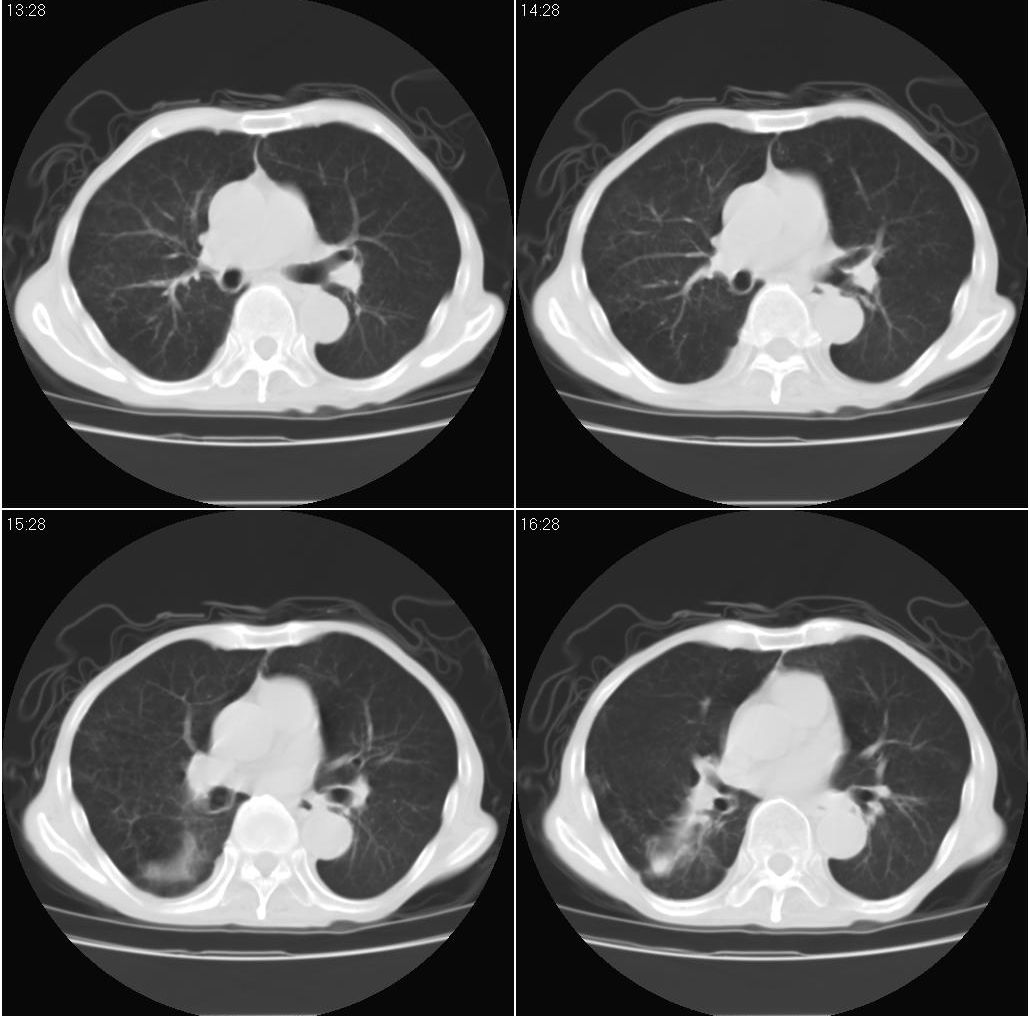

标题: 病例追踪

该患者通过抗炎治疗明显好转:当时患者消瘦,实是因为患者进食量不多。患者有食道癌,因发生原发肺癌的机率并不高,当时的ct片除了增强感觉有强化外(其实这信息也并不确定,因为是外院ct),其实并没有发现支气管腔改变等直接征象。经过治疗,患者现在一般情况良好。以下是9月22日的复查片,发现病灶吸收明显。纵隔窗就不上传了。

[本贴已被 fanshl 于 2008-9-26 10:52:11 修改过]